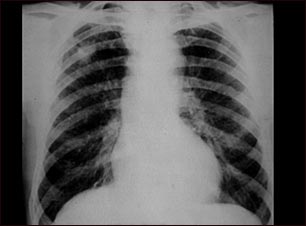

Neumoconiosis del minero, Etapa II #2

Esta radiografía de tórax muestra la neumoconiosis del minero etapa II. A ambos lados del pulmón hay áreas difusas, pequeñas (de 2 a 4 mm. cada una) y claras. En la parte superior del pulmón derecho (al lado izquierdo de la imagen), hay un área clara (mide aproximadamente 2 x 4 cm.), con bordes poco definidos que representa una unificación de áreas claras previamente diferenciadas. Las enfermedades que pueden explicar estos hallazgos en una radiografía son la neumoconiosis del minero (NCM) etapa II, silicotuberculosis, tuberculosis diseminada, cáncer metastásico de pulmón y otras enfermedades pulmonares infiltrativas difusas.